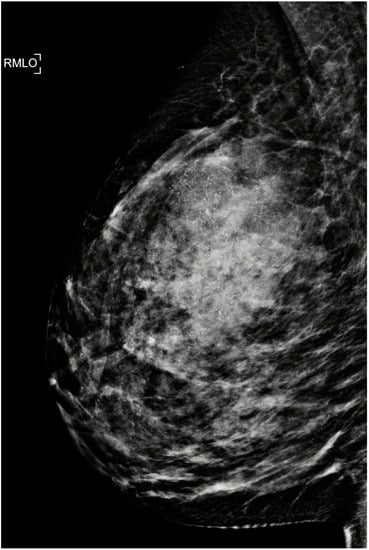

- Park, S.; Yoon, J.H.; Sohn, J.; Park, H.S.; Moon, H.J.; Kim, M.J.; Kim, E.K.; Kim, S.I.; Park, B.W. Magnetic Resonance Imaging after Completion of Neoadjuvant Chemotherapy Can Accurately Discriminate between No Residual Carcinoma and Residual Ductal Carcinoma In Situ in Patients with Triple-Negative Breast Cancer. PLoS ONE 2016, 11, e0149347. [Google Scholar] [CrossRef] [PubMed][Green Version]